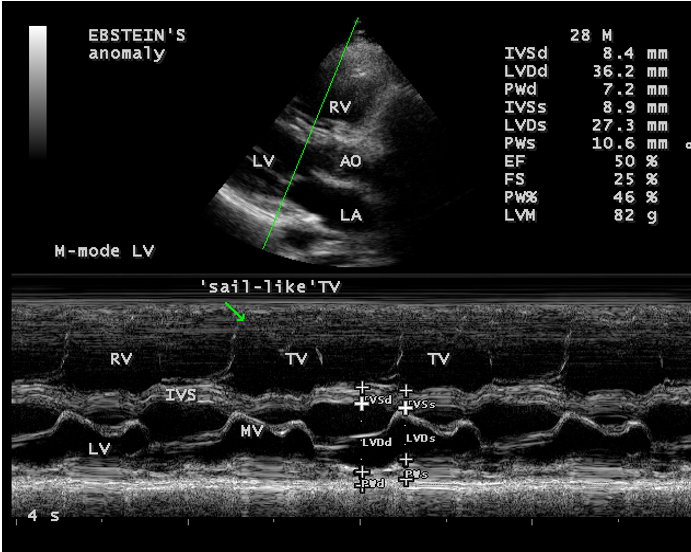

A 28-year old male presented with cyanosis and auscultation revealed a ‘sail sound’ ( loud tricuspid component of first heart sound due to increased tension developed by the large anterior leaflet as it reaches the limits of its systolic excursion- an important sign of anterior leaflet mobility), a ‘cadence’ quality of quadruple rhythm due to wide splitting of first and second sounds ( due to complete right bundle branch block), atrial and ventricular filling sounds (summation of these sounds due to prolonged PR interval). ECG revealed the features of Ebstein’s anomaly as shown in Figures 11 and 12. X-ray chest revealed the Ebstein’s configuration as shown in Figure 13. 2D echocardiography revealed a ‘sail-like’anterior tricuspid leaflet forming a ‘muscular curtain’ in between the inflow and trabecular parts of the right ventricle as an ‘imperforate membrane’ with a ‘pinhole’communication, associated with a muscular VSD (ventricular septal defect) in the proximal, atrialized compartment of right ventricle suggesting an ‘atretic” (‘imperforate’) Ebstein’s anomaly as shown in Figures 14 to 27.

Echocardiographic features Echocardiography is the diagnostic test of choice for Ebstein’s anomaly and the first echocardiographic diagnosis was reported by Lundstrom in 1969. The first diagnostic criteria for Ebstein’s anomaly using a multi-crystal two-dimensional system was defined by Hagan in 1974 [33] and they were able to recognize the apical displacement of the septal tricuspid leaflet and an elongated anterior tricuspid leaflet with increased excursion. The septal leaflet of the tricuspid valve attaches chiefly to the ventricular septum , but part of its basal attachment is to the posterior wall of the right ventricle [34] and it normally exhibits a slight but distinct apical displacement of its basal attachment to the central fibrous body compared to the mitral valve. The distal displacement of septal origin of tricuspid valve seems to be the best echocardiographic criterion as the characteristic sign for Ebstein’s anomaly and the degree of maximal displacement in normal hearts varies considerably with a mean difference of approximately 6 mm with mitral valve. To define the anatomic severity of Ebstein’s anomaly, four-chamber view is the best to demonstrate the apical displacement of septal tricuspid leaflet [35]. The ratio between the mitral-to-apex distance and the tricuspid-to-apex distance varies from 1 to 1.2 in normal subjects and 1.8 to 3.2 in patients and it is 3.6 as in Figure 18 with Ebstein’s anomaly. The true distance in the level of insertion of atrioventricular valves is obtained by substracting the tricuspid-to-apex distance from the mitral-to-apex distance with a mean value of 27.25 ± 12 mm in patients with proven Ebstein’s anomaly and it is 60 mm as shown in Figure 18 compared to reference group (5.7 ± 2 mm). Kambe and coworkers calculated the distance between both atrioventricular valves directly as a mean value of 21 mm with a range of 14 to 32 mm [36]. A maximum difference in the level of valve insertion of >15 mm in children and >20 mm in adults is discriminated between normal and Ebstein’s anomaly [37],[38]. Despite this fact, a patient with an ‘unequivocal’ Ebstein’s malformation can be encountered in whom the diagnosis cannot be made with certainity solely on the basis of apical displacement of the septal tricuspid valve leaflet. Occasionally, the leaflet attaches to the trabecular part rather than the inlet part of the septum, the conventional four-chamber view will not reveal any septal insertion as shown in Figures 28 and 29.

The anterior tricuspid leaflet is not involved in the process of downward displacement, it may be abnormally inserted occasionally and Shiina, et al documented the apical displacement of anterior tricuspid leaflet in 14% of cases echocardiographically [39]. The anterior leaflet forms a large, sail-like intracavitary curtain as in Figures 14, 25 and contains muscular strands instead of consisting entirely of a fibrous membrane as in the normal tricuspid valve [40]. It is potentially mobile with a brisk sail-like movement as shown in Figure 21 to 24 [41], free bloating with a ‘whipping motion’ across the right ventricular outflow tract (RVOT) as shown in Figure 26 and in some cases, the movement is restricted due to its adherence to the ventricular wall as in Figure 1 and 2, 4 and 9. It is often fenestrated, may in part be musculaized , inserting into the trabeculations of the right ventricle (RV) as in Figure 28 and rarely, the anterior leaflet forms an ‘atretic’ membrane that spans the midportion of the right ventricular cavity as in Figure 16.